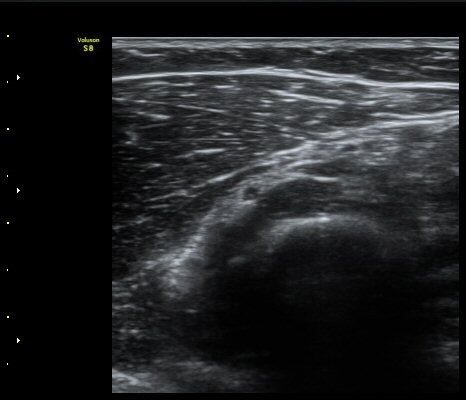

ÃÊÀ½ÆÄ °Ë»ç